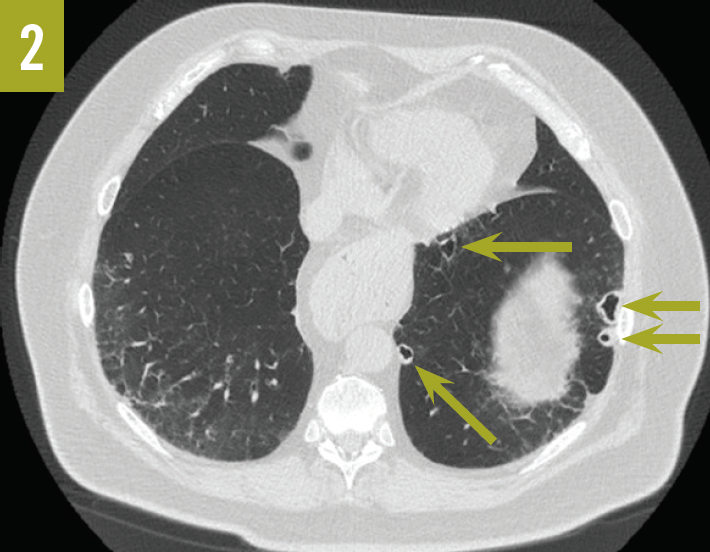

Rheumatoid lung nodules at ct are round or lobulated, several millimeters to several centimeters in size, and often peripheral with mid upper lung predominance. There may be multiple nodules in both lungs. Lung nodules usually cause no signs. Rheumatoid nodules are firm lumps under the skin. They tend to form close to joints in people affected by rheumatoid arthritis. Lungs as a site for the initiation of rheumatoid arthritis (ra). Often called rheumatoid nodules, these benign lumps rarely cause symptoms but occasionally can rupture. These bumps can be as large as a. They are commonly multiple but may manifest as a single nodule. Lung nodules that develop from ra, called pulmonary rheumatoid nodules, are rare.

What Are Rheumatoid Nodules In Lungs Lungs as a site for the initiation of rheumatoid arthritis (ra). Rheumatoid lung nodules at ct are round or lobulated, several millimeters to several centimeters in size, and often peripheral with mid upper lung predominance. Lungs as a site for the initiation of rheumatoid arthritis (ra). Small lumps can form in the lungs (rheumatoid nodules), as well as in other parts of the body. There may be multiple nodules in both lungs. Rheumatoid nodules are firm lumps under the skin. These bumps can be as large as a. They tend to form close to joints in people affected by rheumatoid arthritis. Lung nodules usually cause no signs. Often called rheumatoid nodules, these benign lumps rarely cause symptoms but occasionally can rupture. They are commonly multiple but may manifest as a single nodule. The respiratory system can be less often involved at the upper. Lung nodules that develop from ra, called pulmonary rheumatoid nodules, are rare.

the spectrum of Raassociated lung disease. a A CT image of a What Are Rheumatoid Nodules In Lungs Often called rheumatoid nodules, these benign lumps rarely cause symptoms but occasionally can rupture. Lung nodules that develop from ra, called pulmonary rheumatoid nodules, are rare. Rheumatoid lung nodules at ct are round or lobulated, several millimeters to several centimeters in size, and often peripheral with mid upper lung predominance. Small lumps can form in the lungs (rheumatoid nodules), as. What Are Rheumatoid Nodules In Lungs.